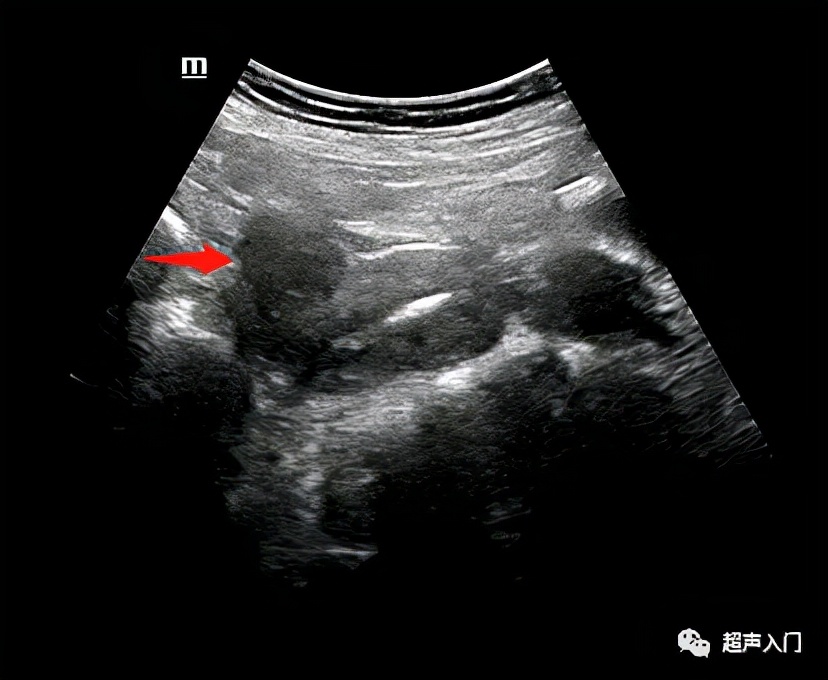

前壁的肌瘤

通常为了准确描述占位位于子宫的那个位置,除了前壁、后壁,子宫也有左侧壁,右侧壁。

但大多数时间大家更常直接描述为前壁、后壁。